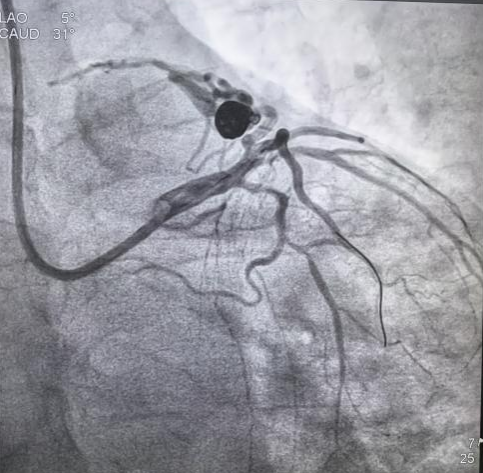

患者杨某近一年来反复有“咽部紧缩”感,多为活动诱发,休息后逐渐缓解,近2周上述症状加重并持续时间延长,严重影响生活质量。就诊我院后完善冠脉造影检查,明确为“冠状动脉-肺动脉瘘”。由我院心血管专家团队进行了充分认真的讨论准备,反复研究、充分论证,考虑该患者“心绞痛”症状与冠状动脉-肺动脉瘘有关,决定对该患者冠状动脉-肺动脉瘘封堵术。经过完善的术前准备于11月23日顺利完成冠状动脉-肺动脉瘘封堵术,术中利用特制微导管将两枚长约30mm弹簧圈置入瘤样扩张内,复查造影示冠状动脉肺动脉分流量明显减少,提示瘘管封堵成功(根据病理生理学机制,预计中远期会完全封堵)。术后该患者症状明显改善,术后第二日出院。

术后影像